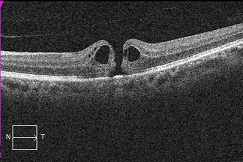

黄斑円孔の手術に関しては、?で記載しましたが、簡単におさらいすると、目の中に器械をいれて、内境界膜という網膜の表層の膜を剥離し、網膜を柔らかくします。その後、目の中に空気を入れてうつ伏せをすることで、円孔の周囲の網膜を浮力で引き寄せて、穴を閉じる。という方法です。

?黄斑円孔で、赤の部分の網膜が硝子体に引っ張られて断裂し、無くなってしまうと、視野の中心部が欠損、見たい部分が見えなくなってしまいます。